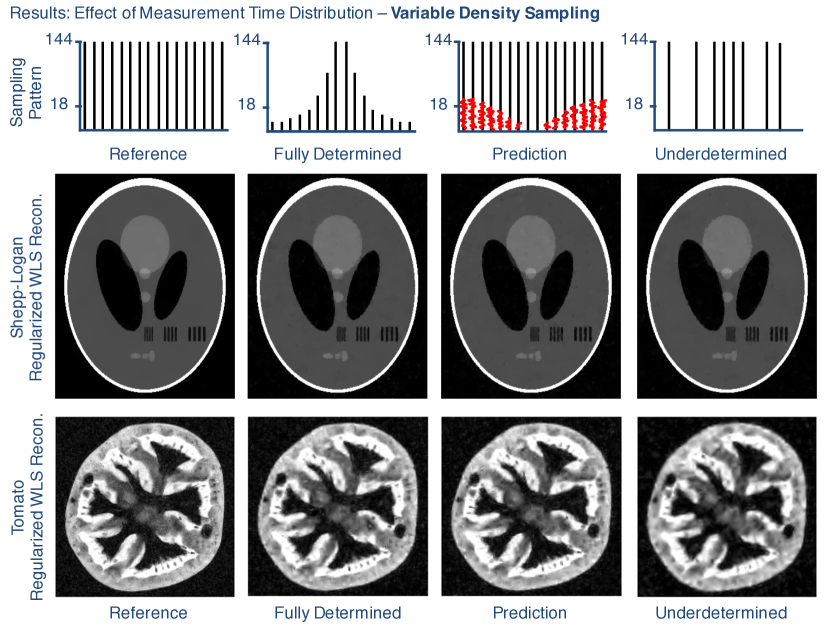

4.1 Effect of Measurement Time Distribution

Fig. 5 shows the results of our experiment to test the effect of various measurement time distributions on reconstruction image quality. For both the Shepp Logan digital phantom and the MRI acquisition of the tomato, the fully determined images with reduced measurement time show lower image quality than the images reconstructed from the reference acquisition data. As seen specifically in the blurred spatial vertical bars, the fully determined images did not fully recover from the limited acquisition time despite not having any corruption from an underdetermined systems of equations.

The variable density underdetermined Shepp Logan reconstruction (Fig. 5, third row, right) was successful and has nearly identically image quality to the fully determined reconstruction but still lower image quality than the reference reconstruction. This indicates that the underdetermined reconstruction recovered well from the underdetermined system, but still could not completely recover from the lower SNR due to reduced measurement time. For the acquired tomato dataset, however, the underdetermined image quality (Fig. 5, bottom, right) is lower than the prediction and fully determined image quality, indicating that the reconstruction could not completely recover from the underdetermined system. This is not a surprising result because the tomato image is not perfectly sparse in the wavelet transform domain, especially when compared to the explicit sparsity of the Shepp Logan phantom in the finite differences domain.

Fig. 5 also shows the results of the image quality prediction process for the same two datasets and sampling distributions. The second and third columns in this figure show that the fully determined reconstructions have essentially identical image quality to their corresponding prediction images. This verifies that the image quality prediction process closely simulates the noise level and reconstructed image quality of the associated fully determined acquisitions.

Refer to caption

Figure 5: Results from the effect of the measurement time distribution experiment using variable density sampling. Each column uses a different set of k𝑘k-space samples; from left to right: over-sampled reference, using all 144 samples at each k𝑘k-space location; variable density, fully determined, using 1/8 of the total samples following a variable density distribution; prediction data, using fully-sampled k𝑘k-space with noise added to simulate the variable density, fully determined dataset; variable density (randomly sampled), underdetermined, using 1/8 of the total samples and following the same variable density distribution, but only using either 144 or zero samples at each location. Row 1: Illustration of how measurement time is distributed across k𝑘k-space. Row 2: WLS reconstruction of the Shepp-Logan data, regularized with total variation. Row 3: WLS reconstruction of the tomato k𝑘k-space data, regularized with wavelets.